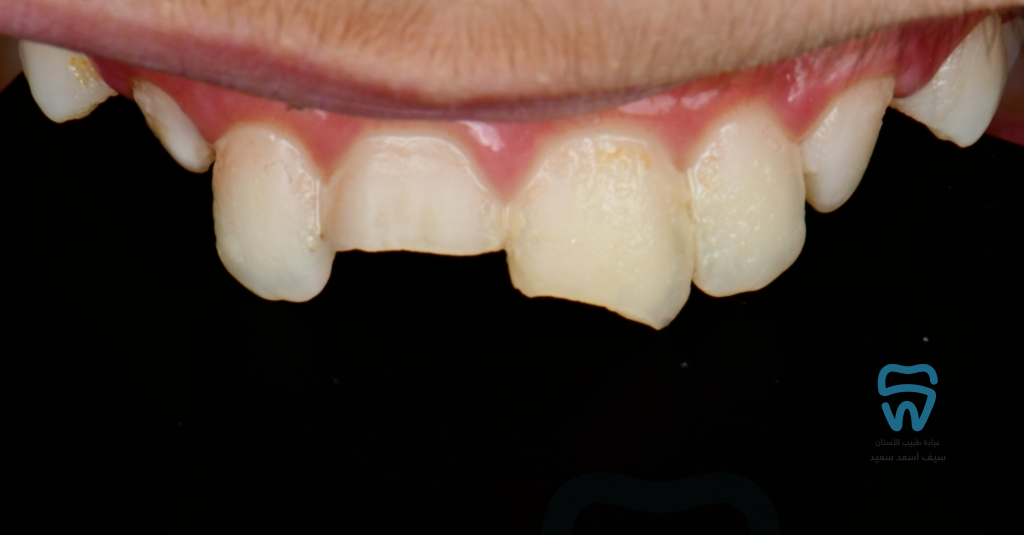

patient came with 2 fractured upper centrals

closer look at the condition

Complicated crown fracture